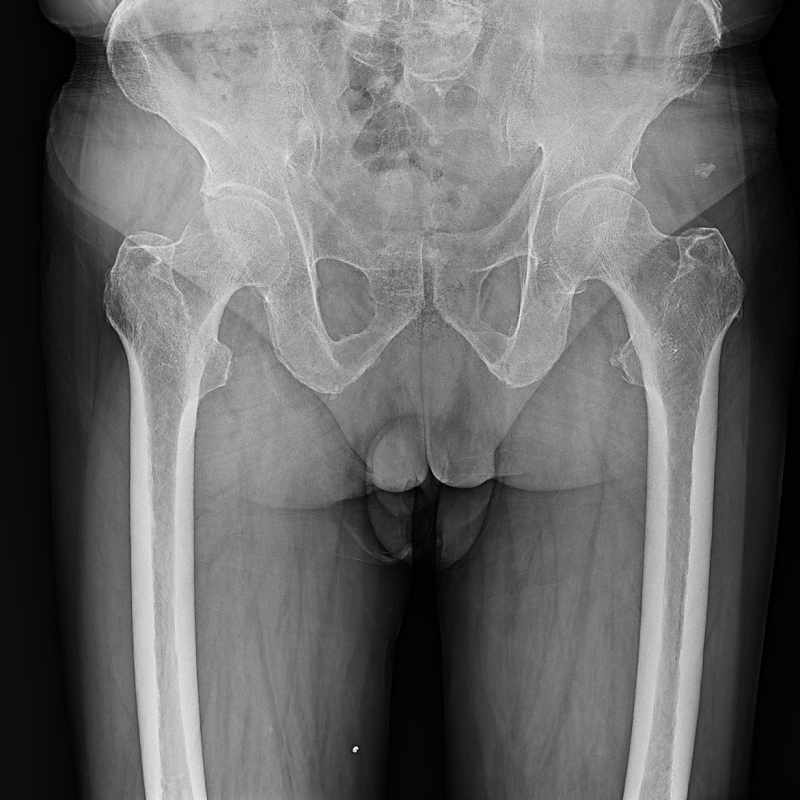

●呈現(xiàn)全下肢或全脊柱圖像

●在脊柱及下肢畸形矯正手術(shù)治療中,為術(shù)前方案制定和術(shù)后復(fù)查提供精準(zhǔn)測量

●有效解決傳統(tǒng)X光片不能一次成像問題,為患者提供更加優(yōu)質(zhì)的醫(yī)療服務(wù)

點(diǎn)片裝置可實(shí)現(xiàn)大范圍縱向移動,高效完成各部位、全身拼接等檢查需求